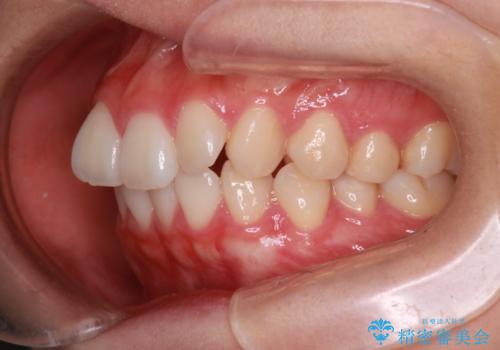

- 前歯の凸凹を主訴に来院されました。

スペースを作るために顎間ゴムを使用して、奥歯の遠心移動をおこない配列しました。

奥歯の遠心移動を行うことで、犬歯関係も良い状態に仕上げることができました。